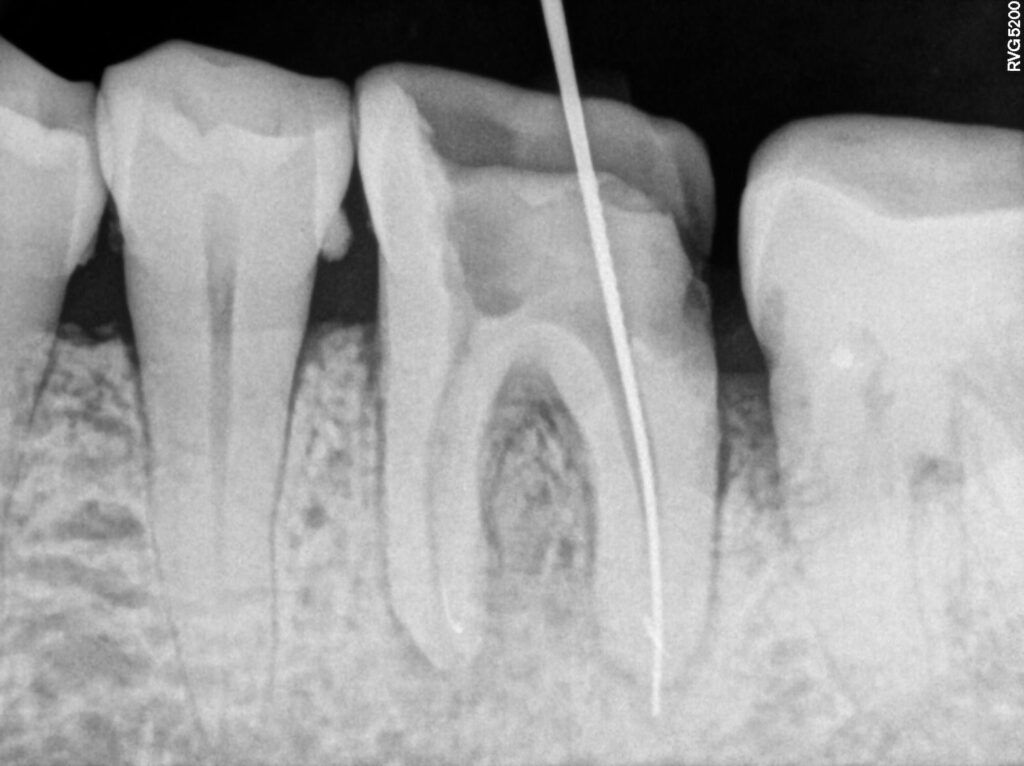

2. Re-Root Canal Treatment at Microdent Dentistry Pune

Re-Root Canal Treatment

Patient Background: Dentist accidentally broke the fine ( instrument ) in one root .. Patient was referred to our practice for re treatment of root canal and retrieval of seperated instrument.

First visit :- Instrument retrieval.. referral case ..

instrument retrieval done successfully and dressing given

Second visit :- pre obturation x ray taken and dressing given with calcium hydroxide

Third visit :- obturation of canals and root canal treatment completed .